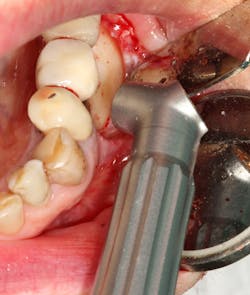

In a recent article discussing two case reports, Nd:YAG and 9.3 micron CO2 lasers were used to detoxify the inner lining of soft tissue surrounding ailing dental implants prior to tissue grafting (figures 1 and 2).12 Lasers can ablate the soft tissue of this particulate (metal) material while killing some of the residual translocated/invasive bacteria, thereby facilitating soft- and hard-tissue healing.

This video demonstrates laser detoxification of the inner lining of the soft-tissue flap, approximating failed dental implant and showing titanium particles embedded into the soft tissue with sparks flying during ablation:

Both the Nd:YAG and 9.3 micron CO2 lasers can have an impact on enhancing soft-tissue healing. Their ability to ablate residual titanium and/or cement from the inner soft-tissue flap lining may help enable the ailing implant sites to successfully heal.